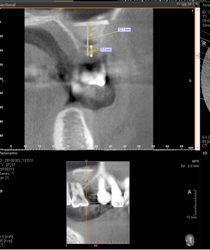

L’implant doit être entouré d’un os suffisant en qualité et en quantité.

Le problème le plus fréquent est un manque d’os, là où l’on souhaite poser un implant.